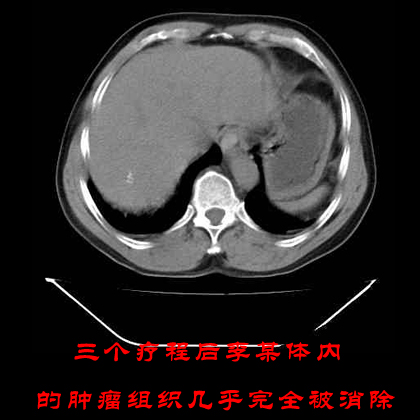

考虑到患者前期接受过放化疗的治疗,并且其身体产生了严重的放化疗副作用,因此我院专家特给予患者李某WB-1无创全身热疗系统的治疗方案,通过这套治疗方案的治疗效果,以期达到帮助患者李某彻底清除肿瘤组织的目的。在李某接受一个疗程的治疗效果后,专家通过CT图发现李某体内的肿瘤组织见明显缩小,遂给李某安排第二期的肿瘤治疗。在李某接受我院WB-1无创全身热疗系统治疗三个疗程后李某的病情完全得到了控制,其病情未出现反复,身体各项技能也均以恢复健康。